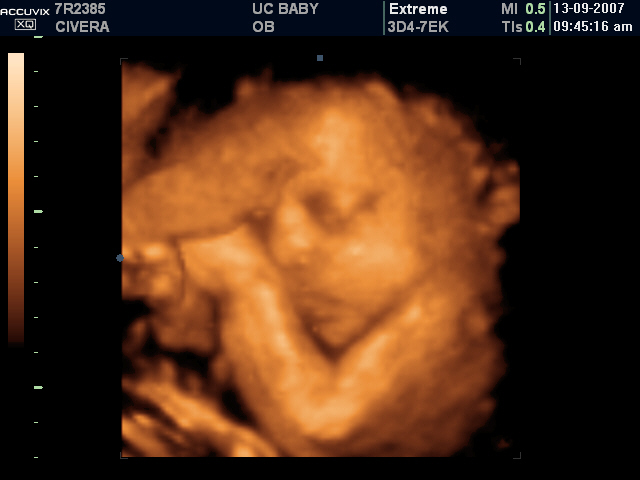

Re-evolution

My starting point... A lot to come.